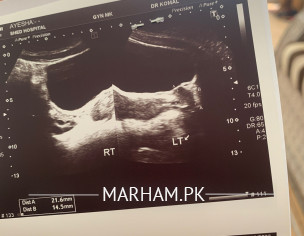

Asking For Self, Female, 22 Years old, north nazimabad

Kindly check my report and reply I’m in tension why is issue? Thankyou